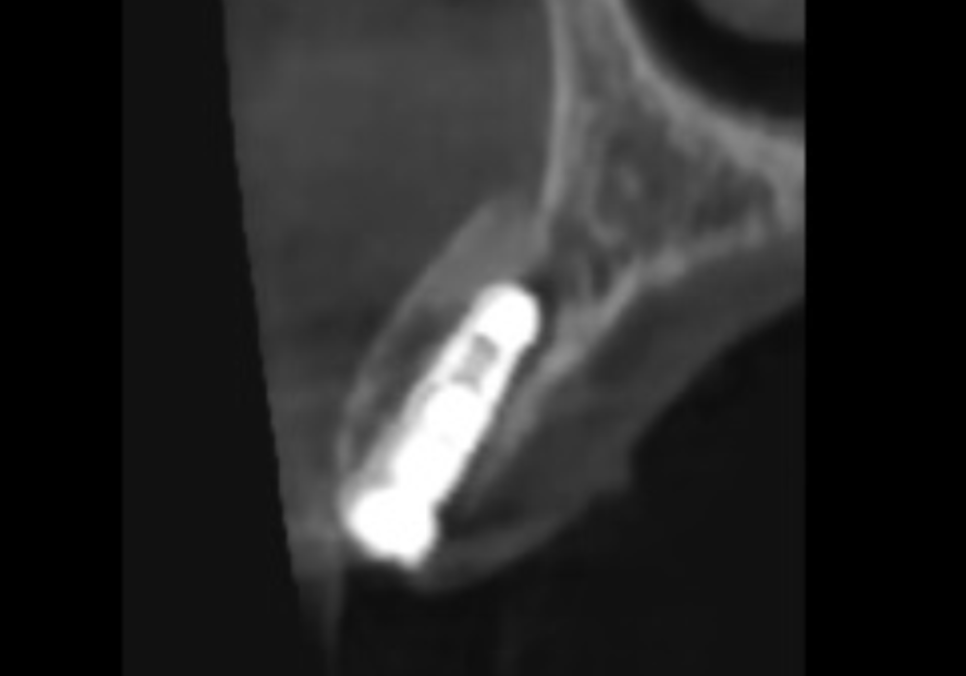

더 큰 문제는 3D CT 상에서

뿌리 끝에 염증이 발견되었다는 점인데요.

뿌리 끝에 이미 염증이 생겨 있었고,

그 염증 때문에 주변 잇몸뼈가 녹아내려

뿌리 끝자락만 간신히 뼈에 걸쳐져 있는 상태였어요.